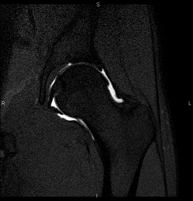

- Hip MRI

Examination for the study of injuries to tendons, muscles and hip joints. Enables early detection of hip osteoarthritis. It is very useful for detecting bursitis and dynamic osteopathy of the pubis, which is common in athletes. It lasts approximately 20 minutes. It is a radiation-free procedure.